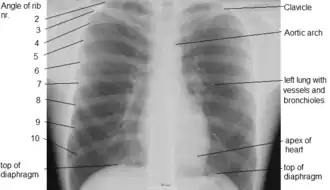

The anatomy of the chest can also be described through the use of anatomical landmarks. The nipple in the male is situated in front of the fourth rib or a little below; vertically it lies a little external to a line drawn down from the middle of the clavicle; in the female it is not so constant. A little below it the lower limit of the great pectoral muscle is seen running upward and outward to the axilla; in the female this is obscured by the breast, which extends from the second to the sixth rib vertically and from the edge of the sternum to the mid-axillary line laterally. The female nipple is surrounded for half an inch by a more or less pigmented disc, the areola. The apex of a normal heart is in the fifth left intercostal space, three and a half inches from the mid-line.